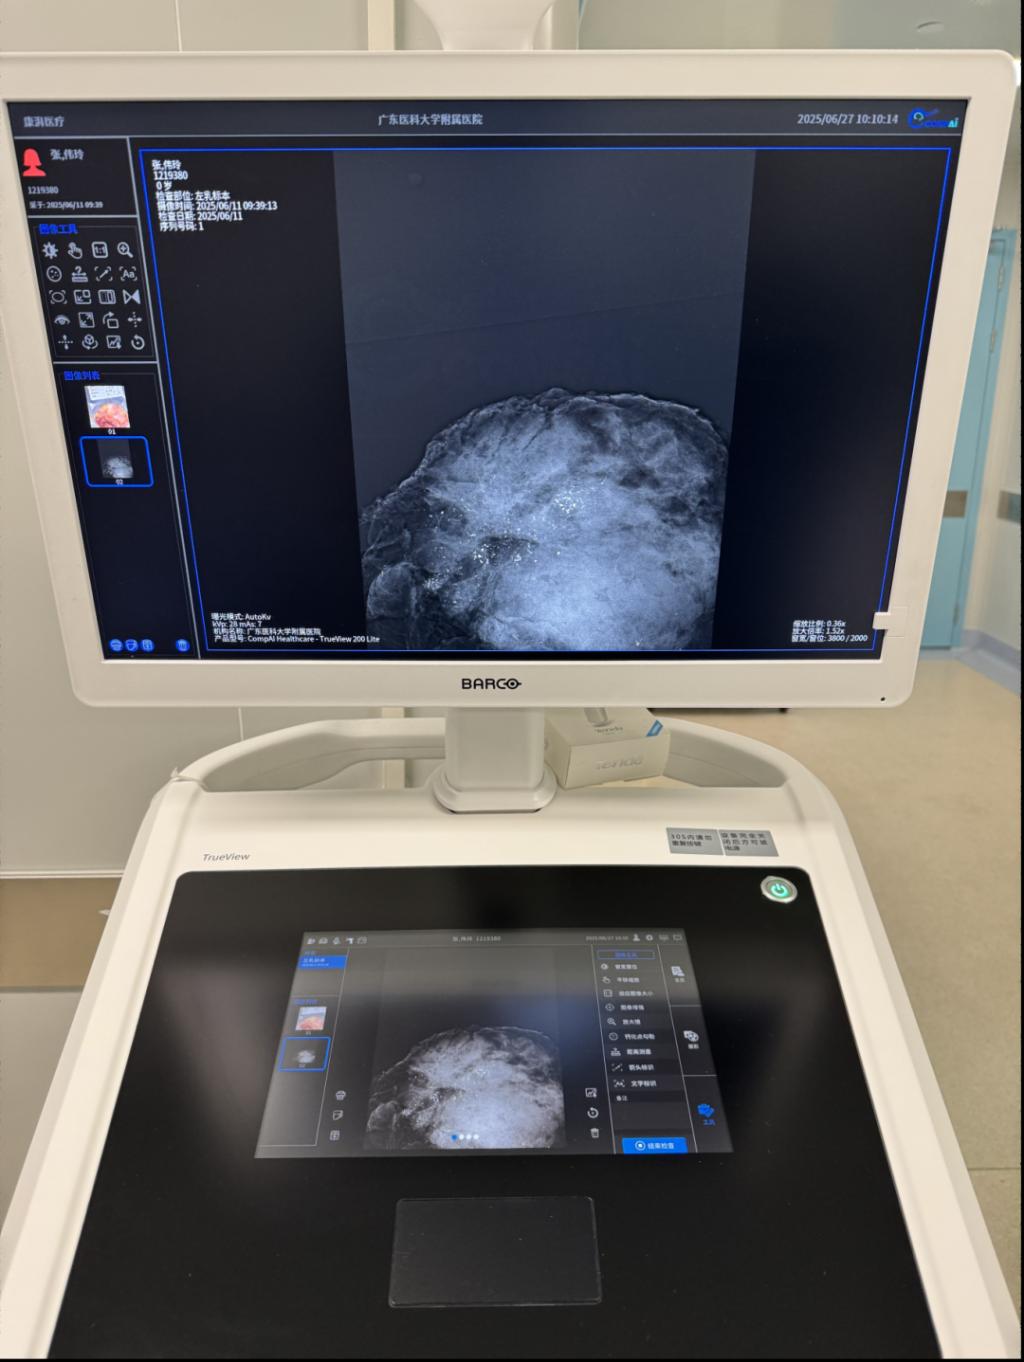

▲术中钼靶设备